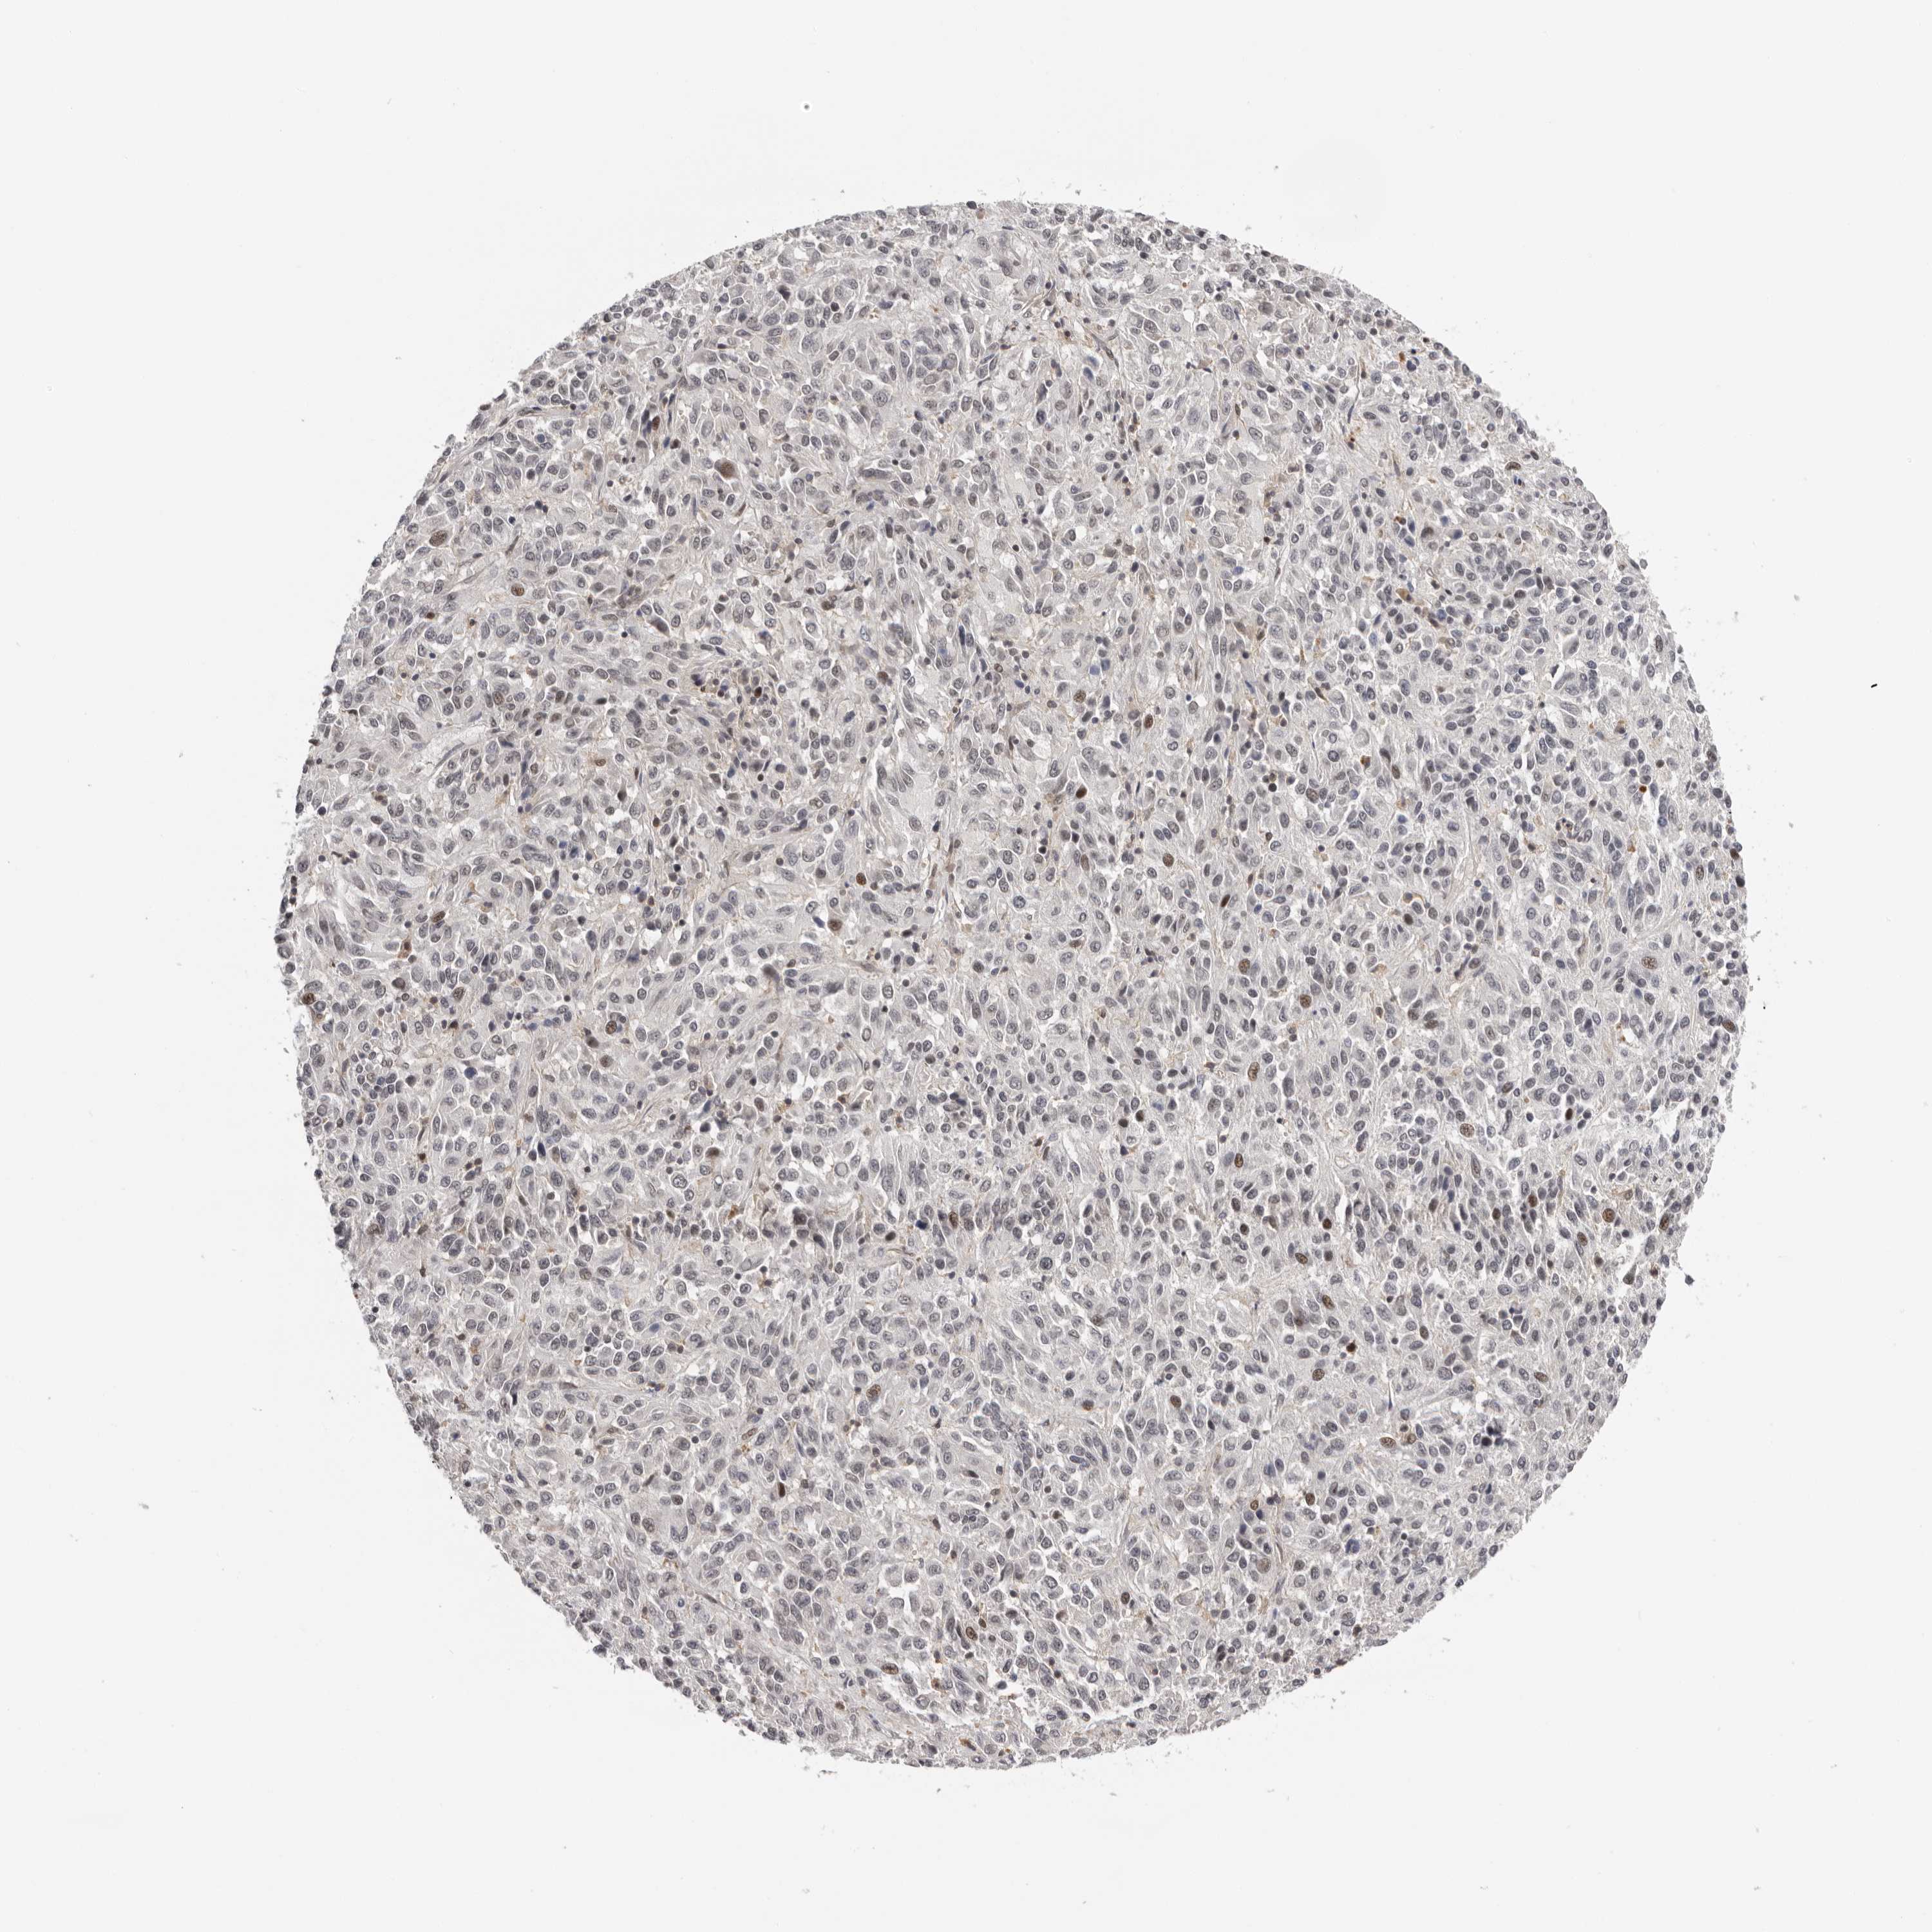

MELANOMA - Protein expressioni

A mouse-over function shows sample information and annotation data. Click on an image to view it in a full screen mode. Samples can be filtered based on level of antibody staining by selecting one or several of the following categories: high, medium, low and not detected. The assay and annotation is described here.

Note that samples used for immunohistochemistry by the Human Protein Atlas do not correspond to samples in the TCGA dataset.

Antibody stainingi

Antibody staining in the annotated cell types in the current human tissue is reported as not detected, low, medium, or high, based on conventional immunohistochemistry profiling in selected tissues. This score is based on the combination of the staining intensity and fraction of stained cells.

Each image is clickable and will lead to virtual microscopy that enables deeper exploration of all samples and also displays staining intensity scores, fraction scores and subcellular localization as well as patient and tissue information for each sample.

Antibody HPA023081

Antibody HPA023103

Antibody HPA024795

Staining

High

Medium

Low

Not detected

Intensity

Strong

Moderate

Weak

Negative

Quantity

>75%

75%-25%

<25%

None

Location

Nuclear

Cytoplasmic/membranous

Cytoplasmic/membranous,nuclear

Malignant melanoma, NOS

Malignant melanoma, Metastatic site